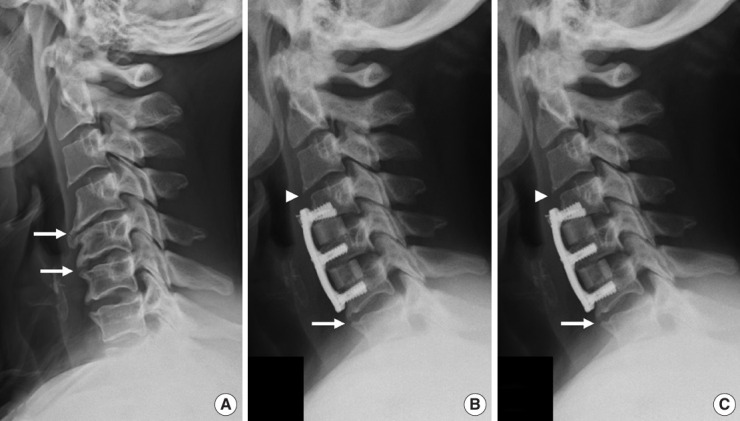

目的:探讨颈椎前路椎间盘切除术融合(ACDF)后邻接层骨化发展(ALOD)的相关因素及相关临床结果。方法:我们回顾性回顾了140例因退行性椎间盘疾病而行原发性ACDF的成年人的记录。我们比较ACDF后有和没有ALOD的患者。术前和至少24个月随访时评估影像学测量和与ALOD相关的因素。临床结果包括临床邻接节段病变(CASP)的发生率、翻修手术和患者报告的结果。结果:与颅侧和尾侧ALOD相关的因素是板到椎间盘距离短(PDD),相邻节段后凸,前凸性ACDF引起的连接节段后凸,以及术前前纵韧带骨化(OALL)。颅ALOD组的平均最终邻接节段运动范围(ROM)(6.9°±2.8°)小于无ALOD组(12°±4.2°)(p < 0.01)。尾侧ALOD组的平均最终邻接段ROM(5.5°±2.4º)也低于无尾侧ALOD组(8.2º±3.7º)(p < 0.01)。与无ALOD的患者相比,尾部ALOD患者的casp手术发生率更高(p = 0.02),而颅侧ALOD患者的casp手术发生率无差异(p = 0.69)。结论:与ALOD相关的因素是与ACDF相邻的后凸节段,前凸融合,术前OALL和短PDD。ALOD与较小的节段性ROM相关,对于尾侧而非颅侧ALOD的患者,CASP翻修手术的发生率较高。

Results: Factors associated with both cranial and caudal ALOD were short plate-to-disc distance (PDD), adjacent-segment kyphosis, hyperlordotic ACDF causing junctional segment kyphosis, and preoperative ossification of the anterior longitudinal ligament (OALL). Mean final adjacent-segment range of motion (ROM) was less in those with cranial ALOD (6.9° ± 2.8°) than in those without cranial ALOD (12° ± 4.2°) (p < 0.01). Mean final adjacent-segment ROM was also less in those with caudal ALOD (5.5° ± 2.4º) than in those without caudal ALOD (8.2º ± 3.7º) (p < 0.01). The incidence of CASP-required surgery was higher in those with caudal ALOD (p = 0.02) but no different in those with cranial ALOD (p = 0.69) compared with those without ALOD.

Conclusion: Factors associated with ALOD were a kyphotic segment adjacent to ACDF, hyperlordotic fusion, preoperative OALL, and short PDD. ALOD was associated with less segmental ROM and, for those with caudal but not cranial ALOD, higher incidence of revision surgery for CASP.